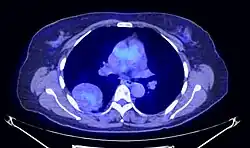

Le TEP scanner est utilisé afin de caractériser l'activité métabolique de la tumeur et de la différencier des tumeurs malignes. Le traceur est fixé de manière hétérogène et peu intense[41],[23].